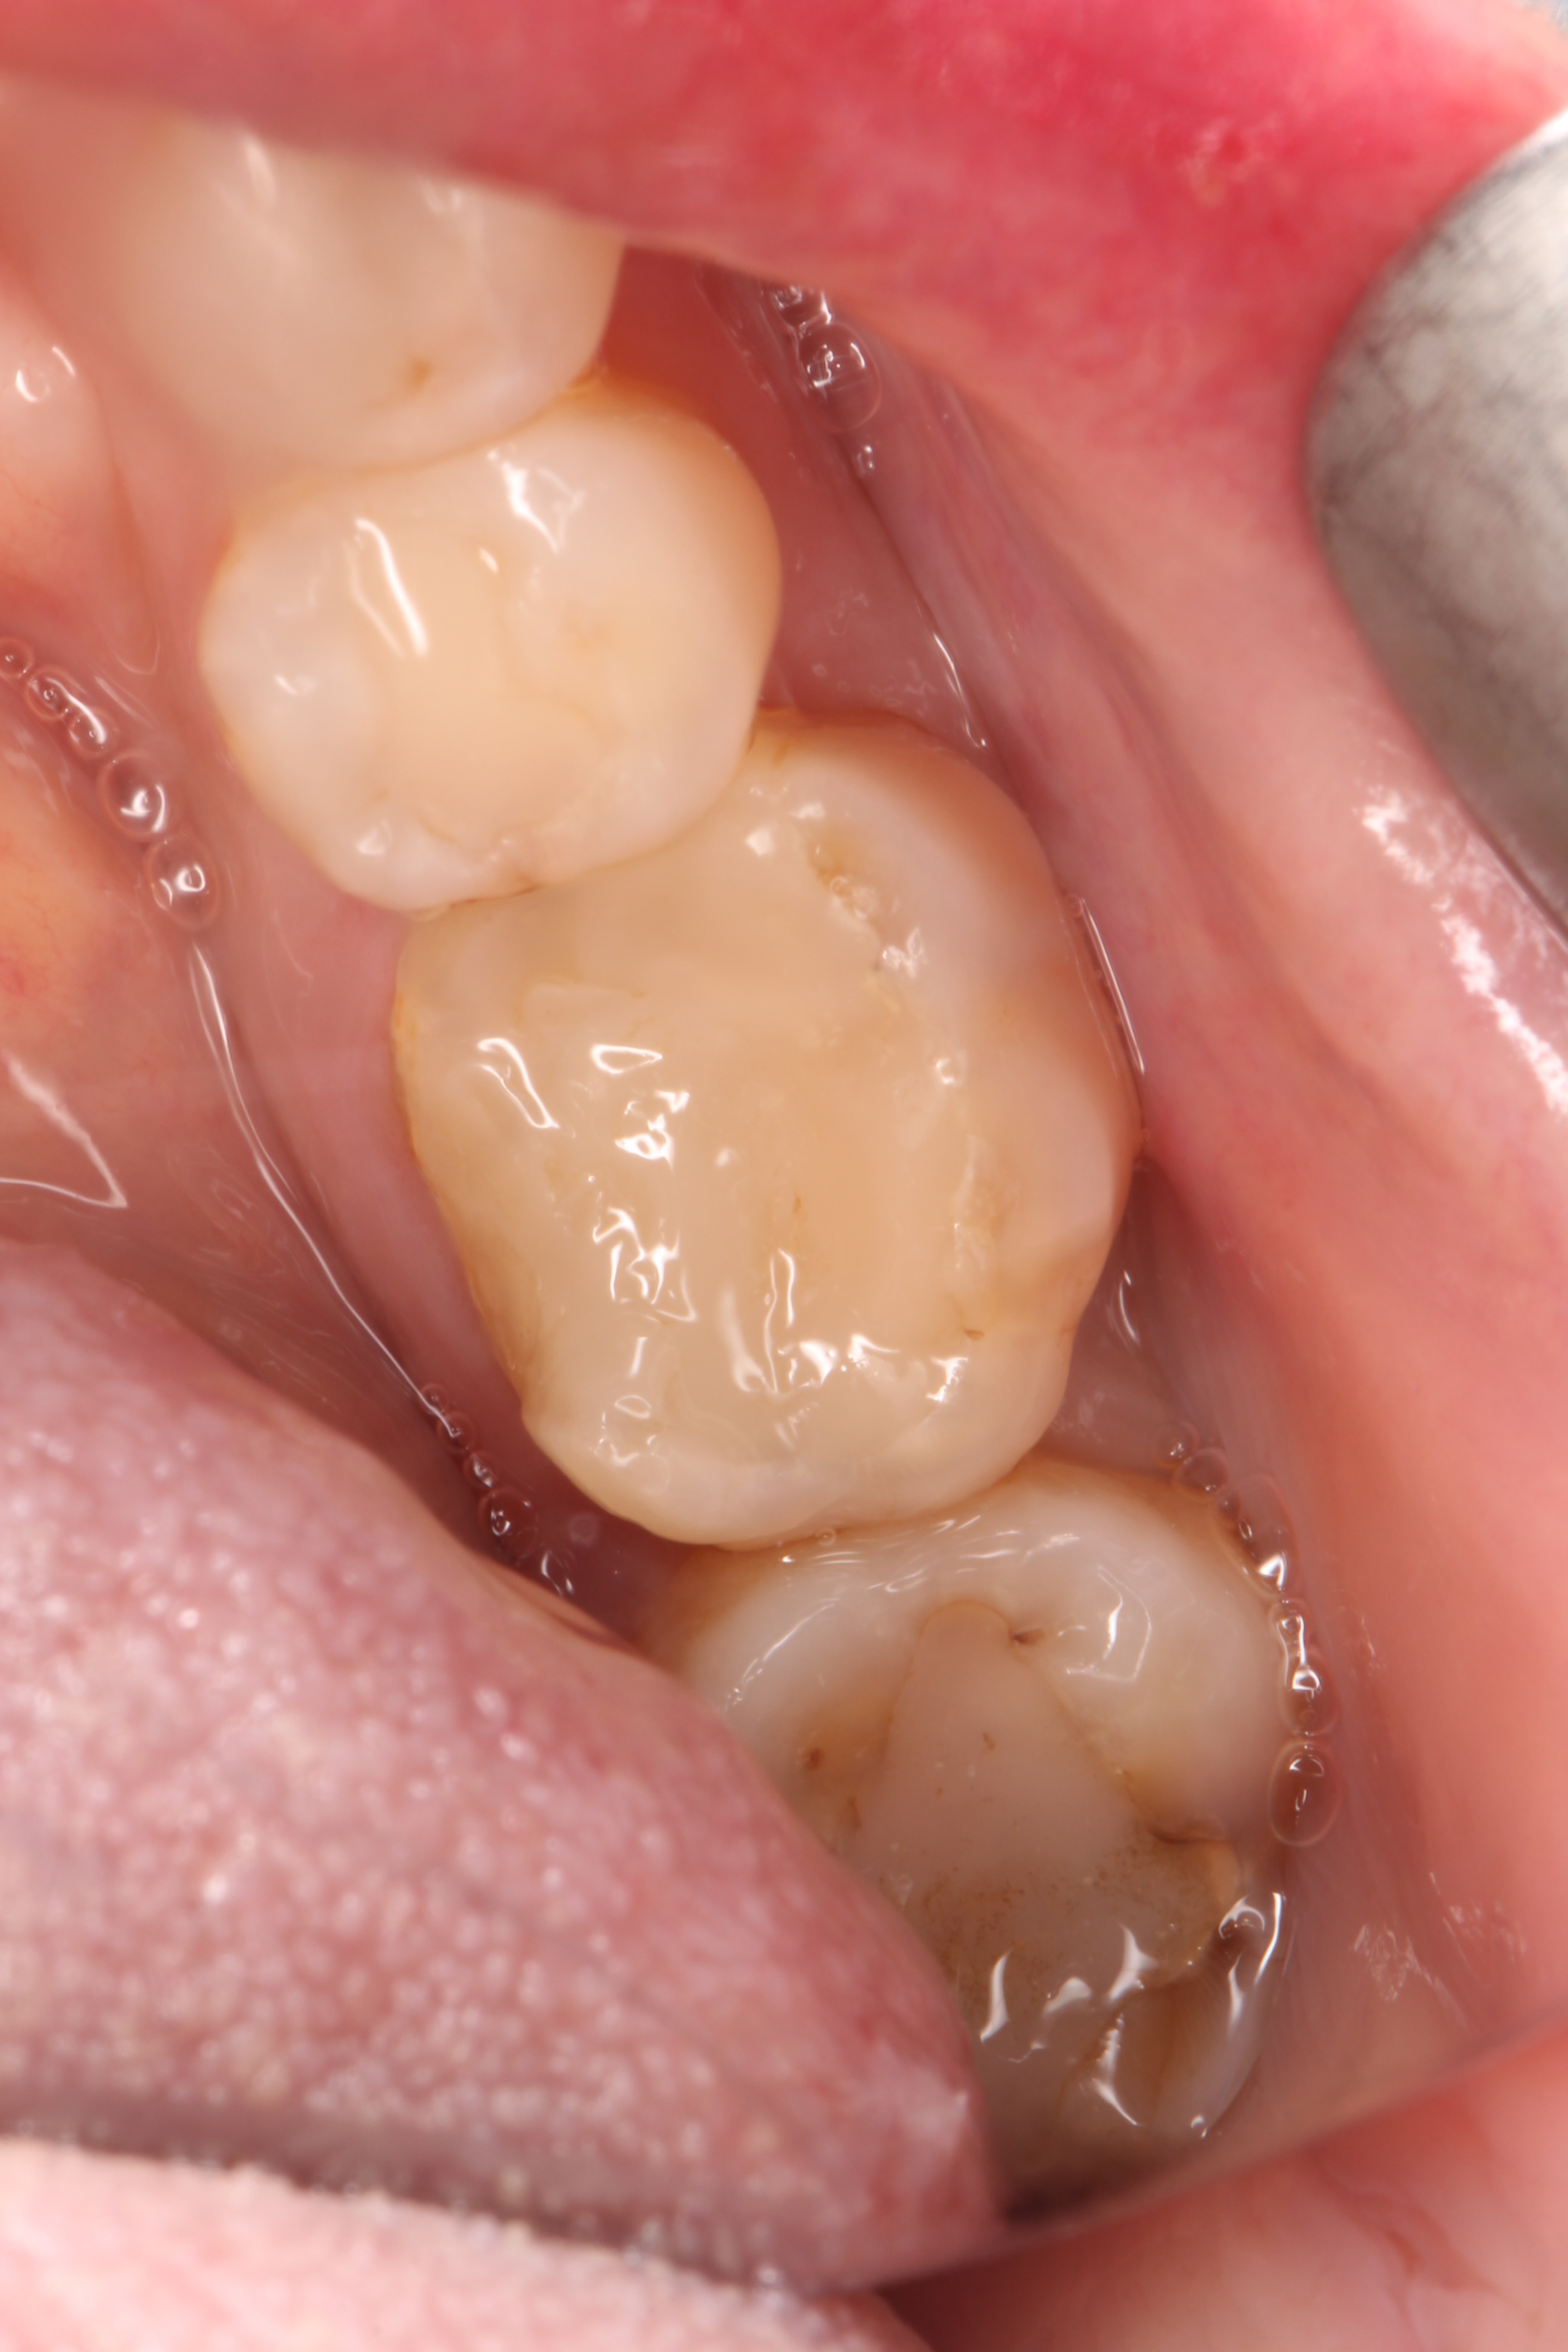

Crowns and onlays by Professor Brian Millar

This course solidified my knowledge and allowed me to practice various cuspal coverage treatments including overlays, onlays and vonlays. I was able to learn about the different preparation techniques and margins required for each indirect material.